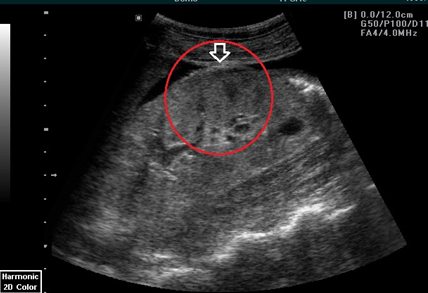

Böbrek tümörü en basit tabirle sağlıklı böbrek içindeki hücrelerin kontrolsüz olarak büyümesidir. Bunlar iyi huylu benign veya kötü huylu malign olarak değerlendirilir. Uzun süren kan basıncı yüksekliği kronik böbrek yetmezliği hastalığı genetik yatkınlık doğuştan gelen at nalı böbrek polikistik böbrek hastalıkları ve sistemik bir hastalık olan von hippel lindau sendromu.

Böbrek tümörü neden olur. Böbrek tümörü hücreleri böbrekte oluşan kanserli dokudan ayrılarak yayılım gösterebilirler. Böbrek tümörleri tedavisi böbrek tümörleri böbreğin her iki kısmında da oluşur ise bu durumun en fazla görüleni parankim etli kısmın tümörleridir. Böbrek fonksiyonlarında bozukluklara yol açan vücudun aşırı yağlanması böbrek kanserine yakalanma riskini artırır. Semptomlar ayrıca vücudun organlarına baskı yapan büyük tümörlerden de kaynaklanabilir.

Check up lar sayesinde kanserin tekrar edip etmediği belirlenecek genel sağlık durumunda herhangi bir değişiklik olursa erken fark edilmesi sağlanacaktır. Böbrek üstü bezi tümörü belirtileri nelerdir. Renal hücreli tümör böbreğin en fazla rastlanan kötü huylu tümörü olup bütün yetişkin kanserleri içinde oranı. Böbrek içindeki hücrelerin dengesiz bir şekilde fazlaca çoğalması ile oluşur.

Böbrekteki tümör eğer malign kötü huylu ise böbrek kanseri olarak adlandırıyoruz. Böbrekteki bu tümörlermalign kötü huylu veya selim iyi huylu olabilir. Adrenal kanser belirtilerine aşırı hormon üretimi neden olur.